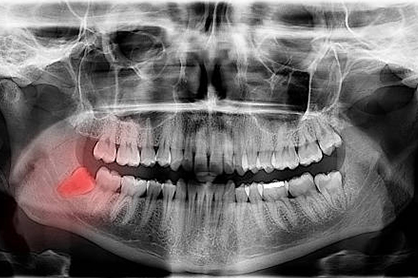

Difficult Cases

- We treat patients when other providers cannot manage.

Severe Bone Loss